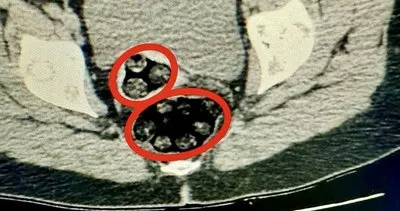

Kars'ta, polisin durdurduğu yolcu otobüsünde hareketinden şüphelenilen İran uyruklu kadının hastanede çekilen röntgeninde, makatında uyuşturucu tespit edildi. Uyuşturucu doğal yolla çıkarılırken, şüpheli...